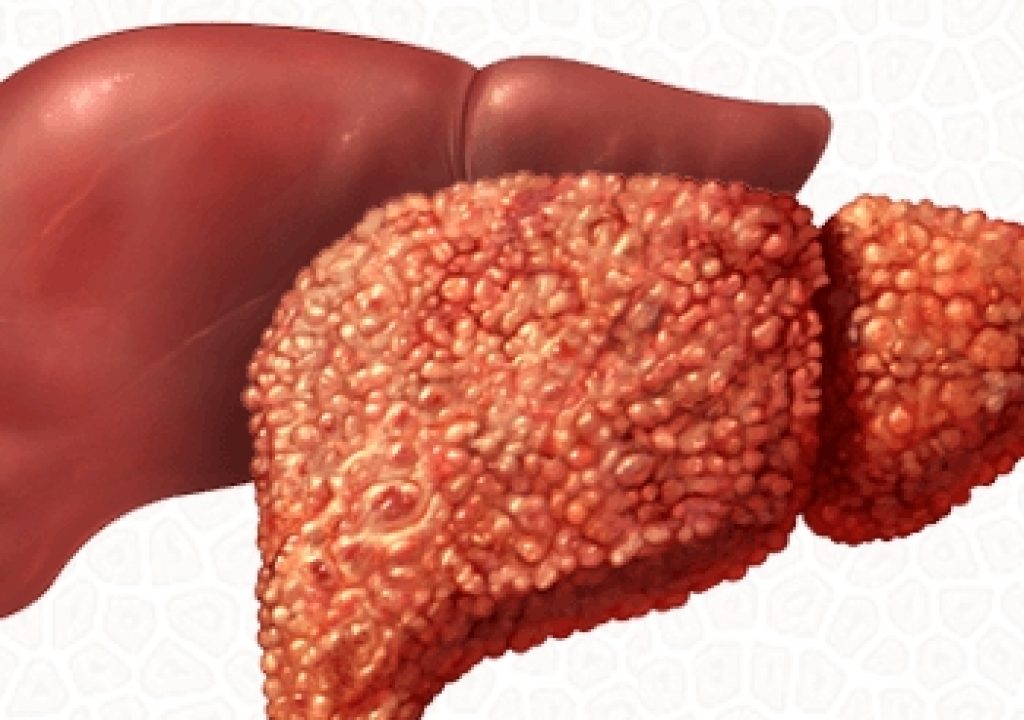

Изображения заболеваний печени: признаки и симптомы